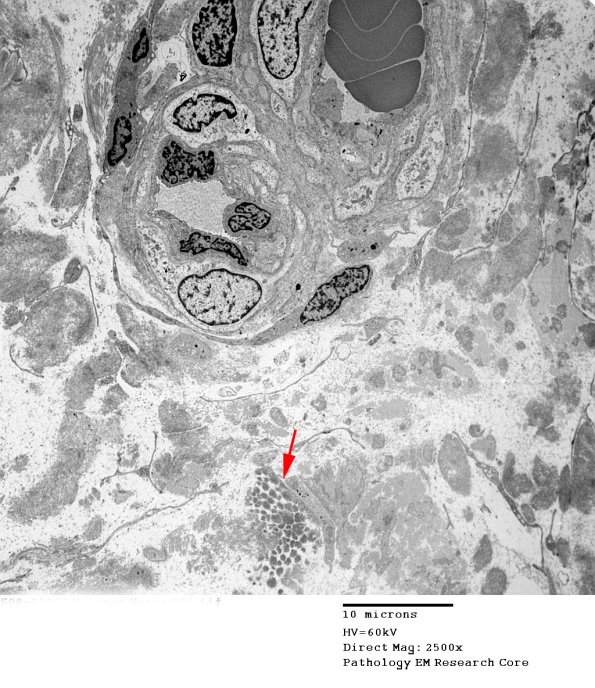

2F12-14 An area (arrow) in which there are collections of processes adjacent to collagen. (electron micrographs)